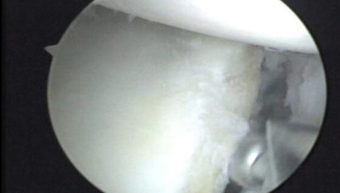

Durante la artroscopía se comprueba la existencia de la lesión de Hill Sacks, la cual es una lesión osteocondral por las luxaciones anteriores que ha sufrido el paciente